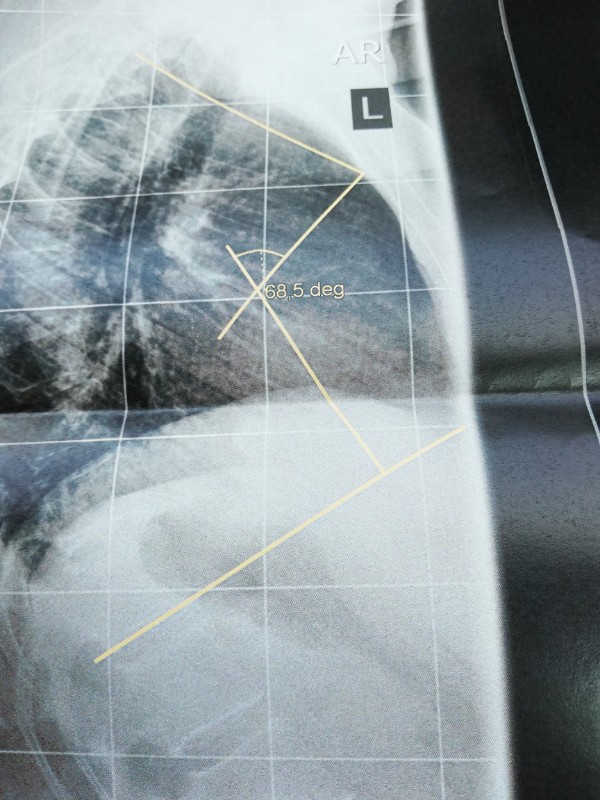

Nachdem ich gestern bei Dr. AL Alwan in Bottrop war, bin ich heute direkt in Oberhausen zum Röntgen der seitlichen Wirbelsäule gefahren. Dr. Al Alwan ist der Ansicht meine Beschwerden könnten von einer Kyphose kommen. Ich bin 54 Jahre alt und habe seit ca 2 Jahren teilweise unerträgliche Schmerzen. Meine Hausärztin ist der Meinung die Schmerzen sind somatoform und mein bisheriger Orthopäde löst mir regelmäßig Blockaden und rät mir zu Sport und Yoga. Leider werden die Schmerzen dadurch schlimmer. Ein MRT 2018 ergab eine leichte Skoliose und eine leichte Kyphose. Leider konnte ich heute mit keinem Arzt über das Röntgenbild sprechen. Es sind Winkel mit 68,5 deg eingezeichnet. Sagt das jemanden was? Es steht nichts von Cobb o. ä. dabei. Ich bin ziemlich ratlos ob das die Ursache der Schmerzen sein könnte. Freue mich über jede Erfahrung oder Tipp von euch. Falls es klappt lade ich mal 2 Bilder hoch. LG und ein schönes, sonniges Wochenende

68,5 Grad könnte sich auf die Hyperkpyhose beziehen, eine normale BWS Kyphose liegt im Bereich 25-40 Grad.

Dr. AL Alwan war nach der Untersuchung der Meinung, dass die Skoliose nicht sonderlich ausgeprägt wäre und mein Rücken sichtbar rund sei. Deshalb die Überweisung zum Röntgen um die Kyphose zu vermessen. Allerdings wurde nur eine seitliche Aufnahme der gesamten Wirbelsäule gemacht. Den Ausdruck und eine CD vom BWS - MRT von 2018 habe ich in seinen Briefkasten geworfen, ich denke nächste Woche weiß ich mehr. Mir ist nur nicht klar ob die 68,5 ged mit Cobb gleichzusetzen sind